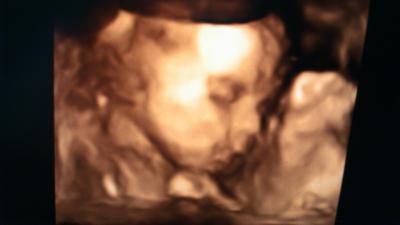

Ihr lieben ich bin so verliebt in meinen kleinen Jonas Ich bin so Stolz und kann den Mai nicht mehr ab erwarten :-)

Bild zu Wieder da vom 3D US :-) + Bild - Forum für Mai - Mamis

Super süsses Bild von deinem Prinzen Nicht mehr lange und wir können alle kuscheln